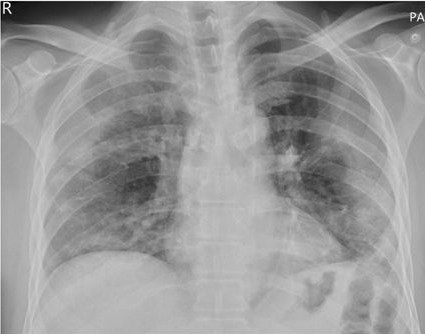

The most common imaging technique used as the first clinical step for chest-related diseases is CXR [26]. Hence, more CXRs could be collected publicly than CT images. A batch of randomly selected samples from the dataset with frontal view, also known as anteroposterior (AP) or posteroanterior (PA), is shown in Fig. 1.

Figure 1: Randomly selected frontal CXR images from different sources